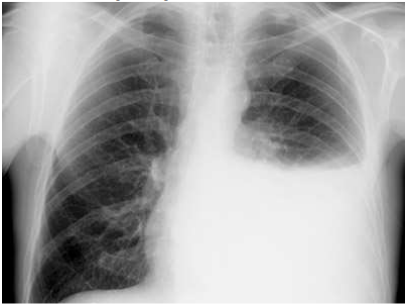

Paciente T.S., 47 anos, masculino, deu entrada no Pronto Atendimento de um Hospital Regional apresentando febre, dor torácica à esquerda (E), com sensação de peso no hemitórax e mal-estar geral. Tabagista 15 anos/maço, nega outras patologias. Relata que está em tratamento com antibióticos há 7 dias por apresentar febre e tosse com expectoração mucopurulenta. Houve redução da expectoração, mas mantinha quadro febril. Ao exame físico, paciente dispneico, redução da expansão toracopulmonar à E, MV e FTV abolido na porção inferior E, com macicez a percussão.

Foi realizado Rx de tórax, conforme figura a seguir:

O quadro clínico é indicativo de